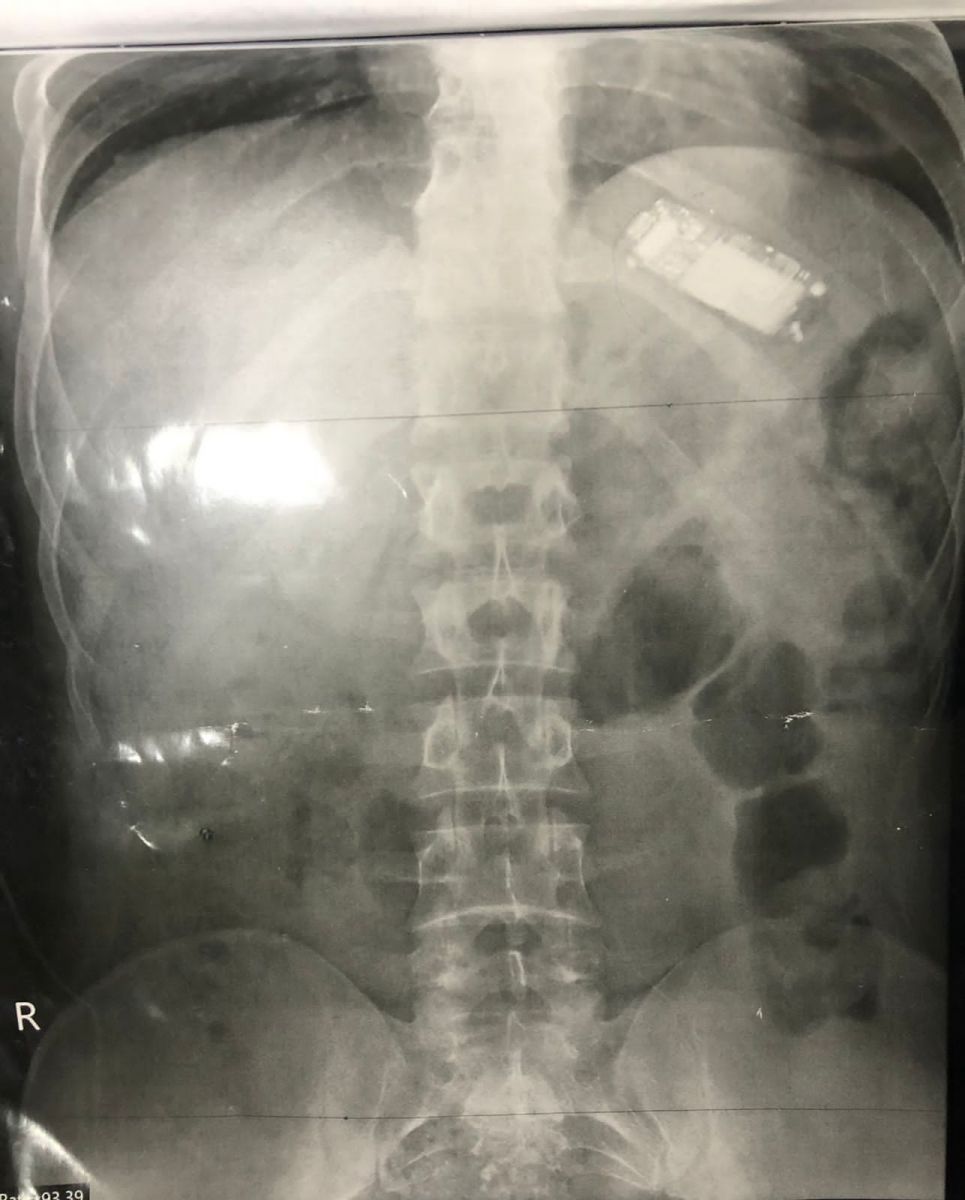

تمكن فريق طبي بمستشفى الباطنة التخصصي بجامعة المنصورة، اليوم الثلاثاء، من استخراج تليفون محمول من بطن شاب باستخدام المنظار الطبي، بعد أن ابتلع الشاب التليفون وظل بداخل المعدة لأكثر من شهرين، ويعاني من آلام شديدة وفقدان للوزن، إلى أن حضر إلى المستشفى وتمكن فريق طبي من استخراج التليفون.

وأكدت الدكتورة أسماء جميل، مدرس بقسم الكبد والجهاز الهضمي والمناظير جامعة المنصورة، أن الشاب يبلغ من العمر 23 عامًا، وقد ابتلع التليفون ولم يتمكن من استخراجه لأن التليفون كان كبير الحجم، وظل داخل المعدة، ووصل إلى مستشفى الباطنة التخصصي بجامعة المنصورة، وأخبر الأطباء أنه ابتلع هاتفًا محمولًا منذ ما يقرب من شهرين، ولم يخبر أحدًا حتى تزايدت آلام المعدة، وبدأ في فقدان الوزن.

تم إجراء الفحوصات الطبية اللازمة من أشعة وتحاليل، وتم اكتشاف وجود التليفون المحمول داخل بطن المريض.